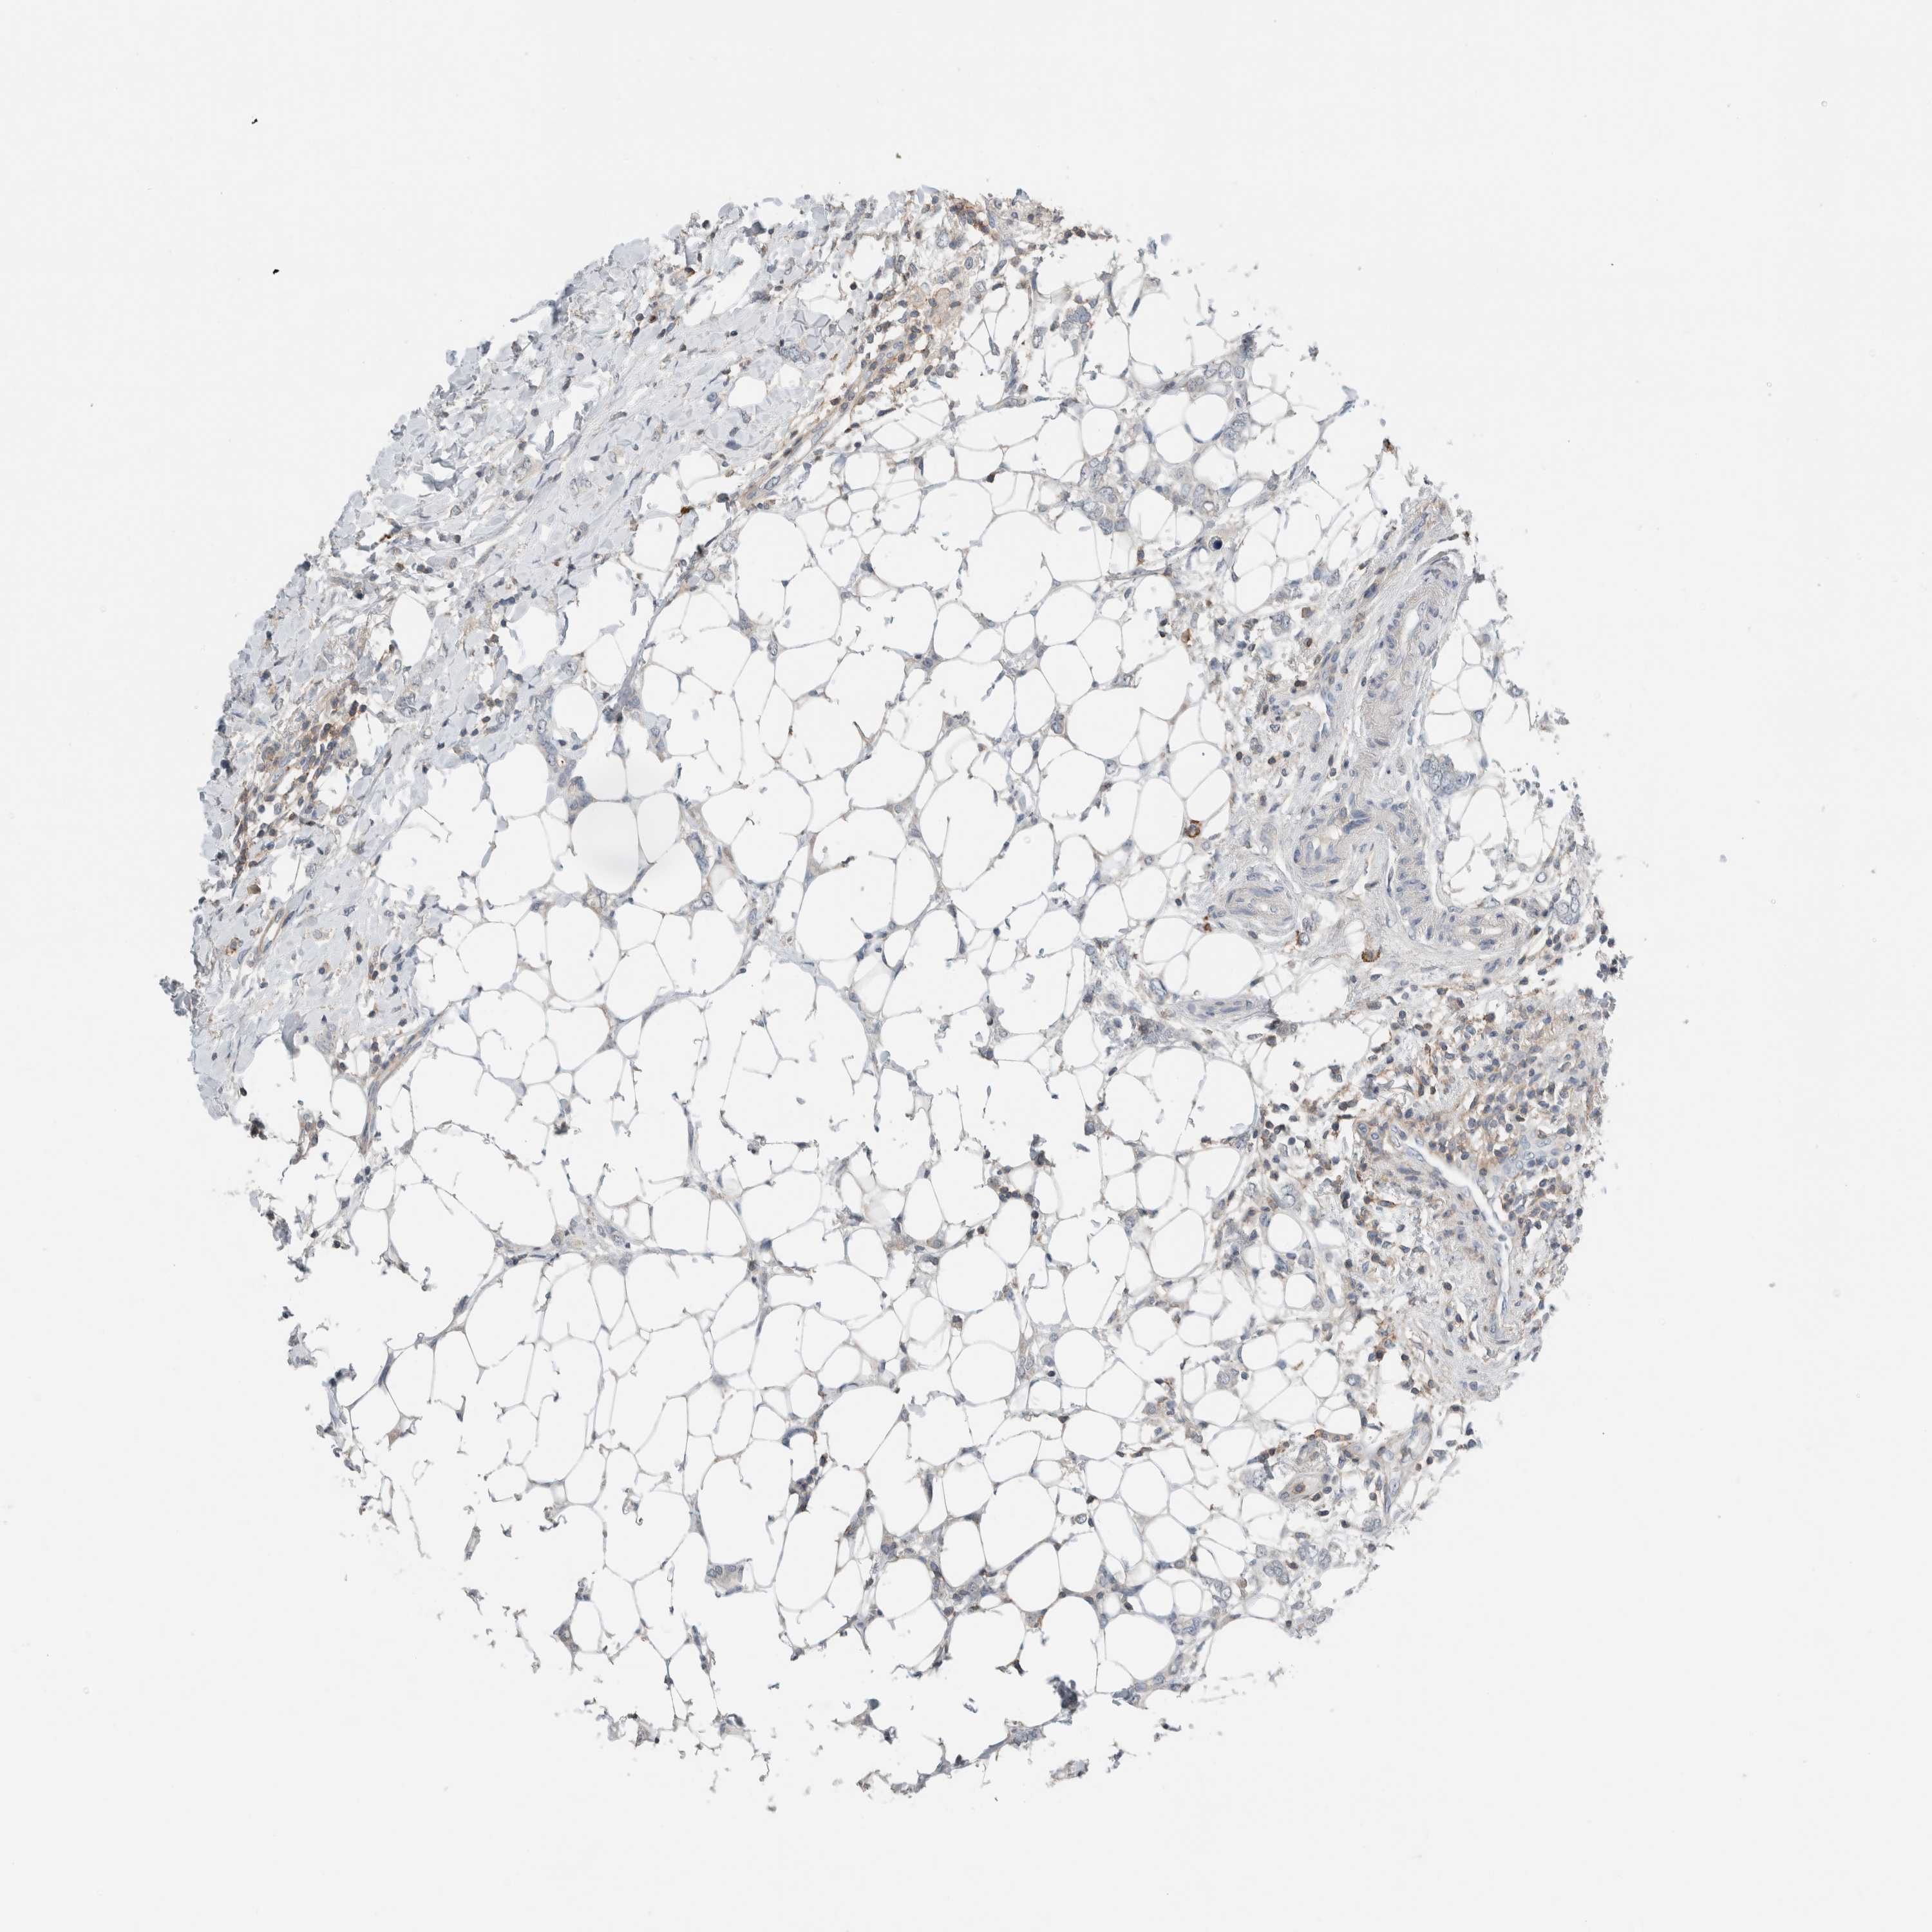

BRCA TCGA BRCA VALIDATION PROTEIN EXPRESSION

Breast cancer

Human cancer

TCGA RNA samplesi

RNA-seq data is reported as average FPKM (number Fragments Per Kilobase of exon per Million reads), generated by the The Cancer Genome Atlas (TCGA) .

Normal distribution across the dataset is visualized with box plots, shown as median and 25th and 75th percentiles. Points are displayed as outliers if they are above or below 1.5 times the interquartile range. FPKM values of the individual samples are presented next to the box plot.

Average pTPM 3.5

Number of samples 1022